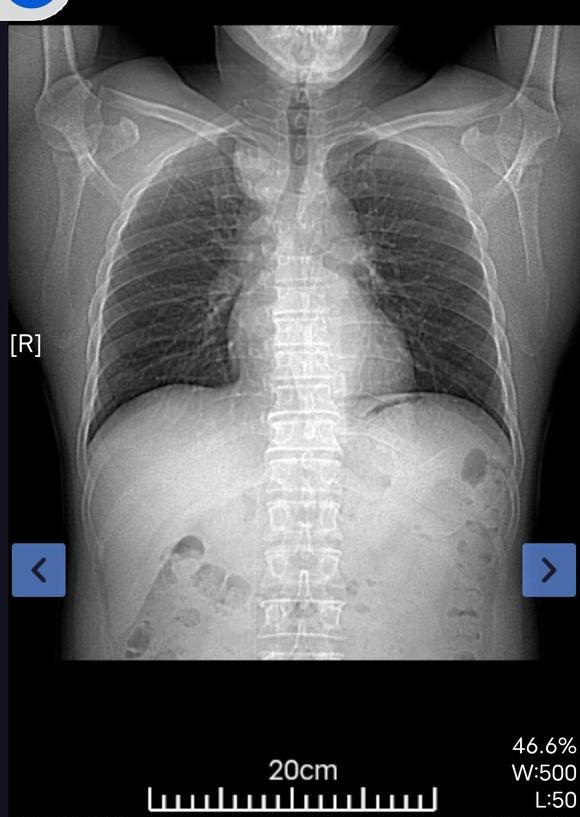

我父亲体检时发现有肿块。到人民医院检查结果显示食管囊肿或支气管囊肿本来医生说不是很大的手术。几天前做了增强ct。又说有可...